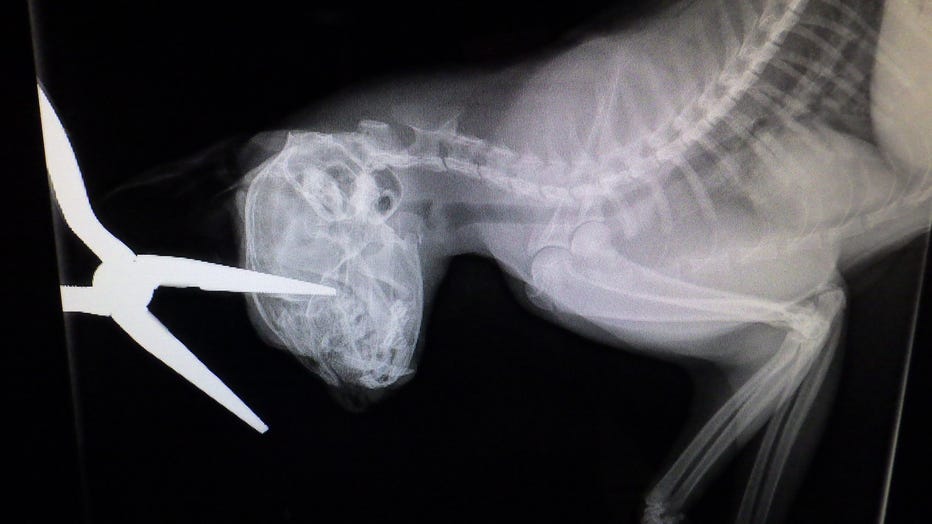

An X-ray after a cat is stabbed in the head with pliers. (Credit: Indianapolis Animal Care Services)

The Indianapolis Animal Care Services (IACS) said the female gray and white short-haired feline was brought to their care after a resident found her. The resident was feeding the cat when she noticed the animal was stabbed in the head with a pair of needle-nose pliers.

A veterinarian removed the pliers and provided emergency care.

The cat is listed in critical condition. The next 24 hours should provide an update on the cat's prognosis.